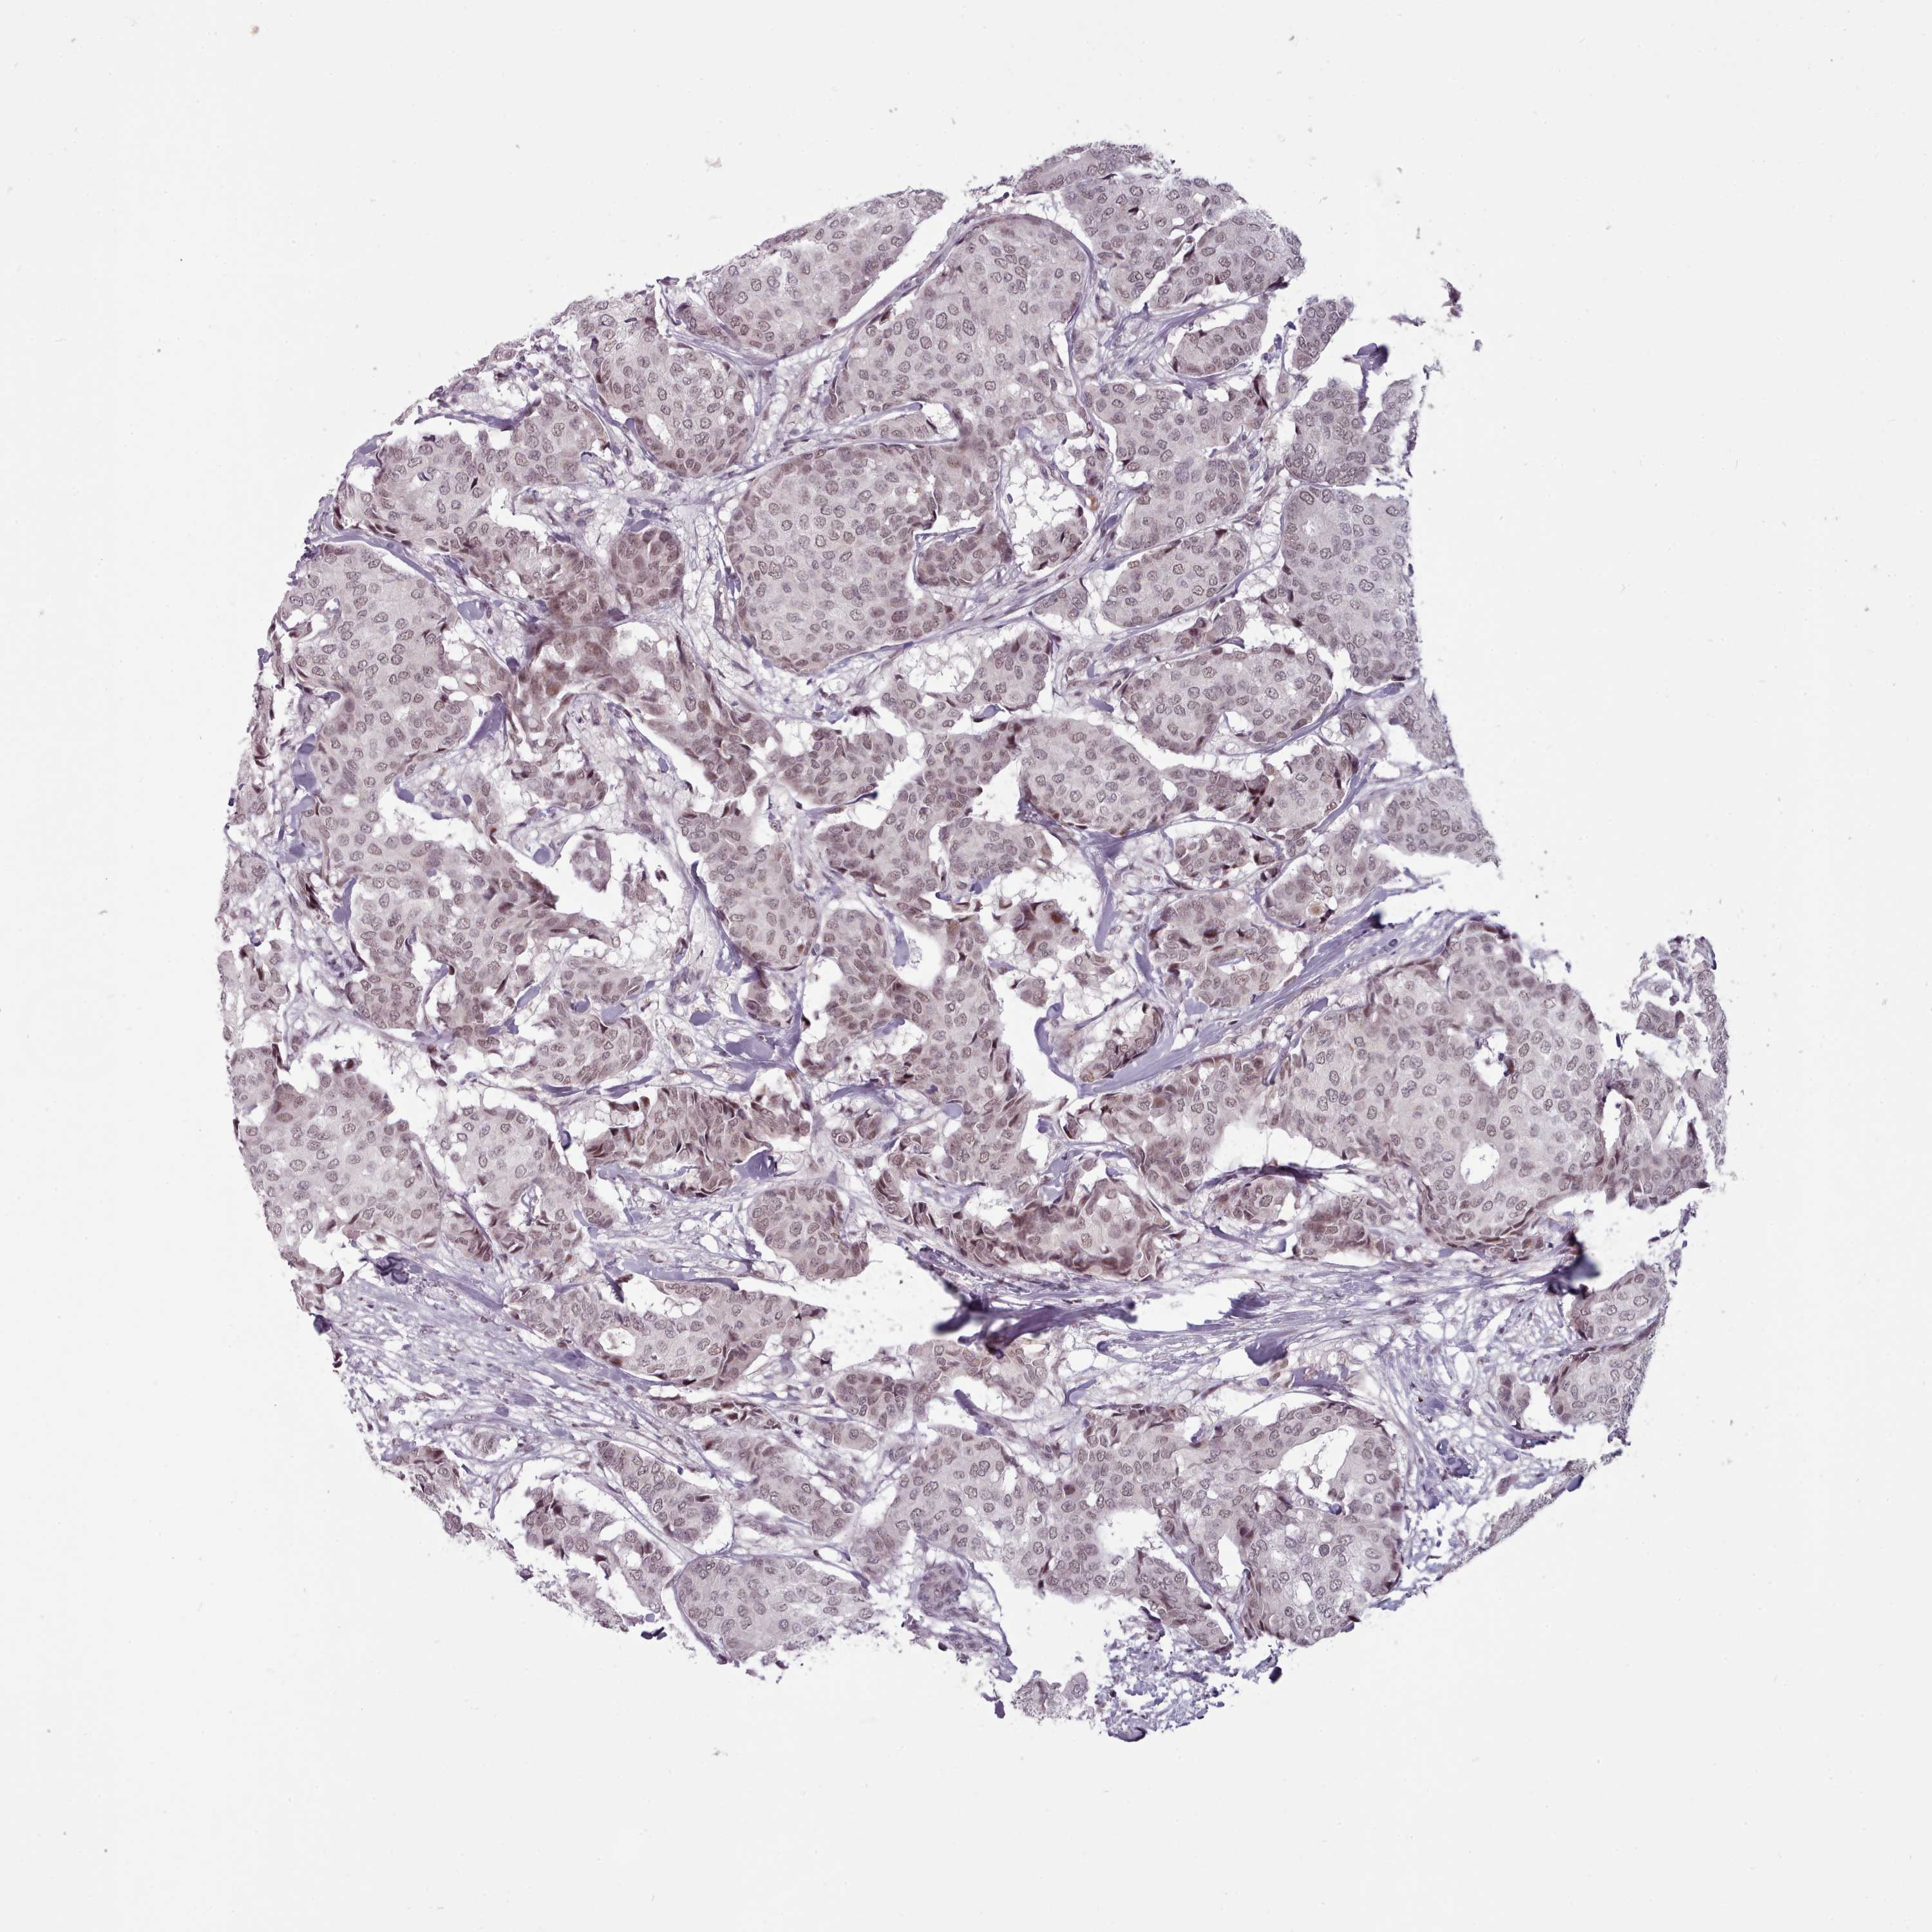

Breast cancer

Breast invasive carcinoma

SRSF9 is not prognostic in Breast Invasive Carcinoma (TCGA)